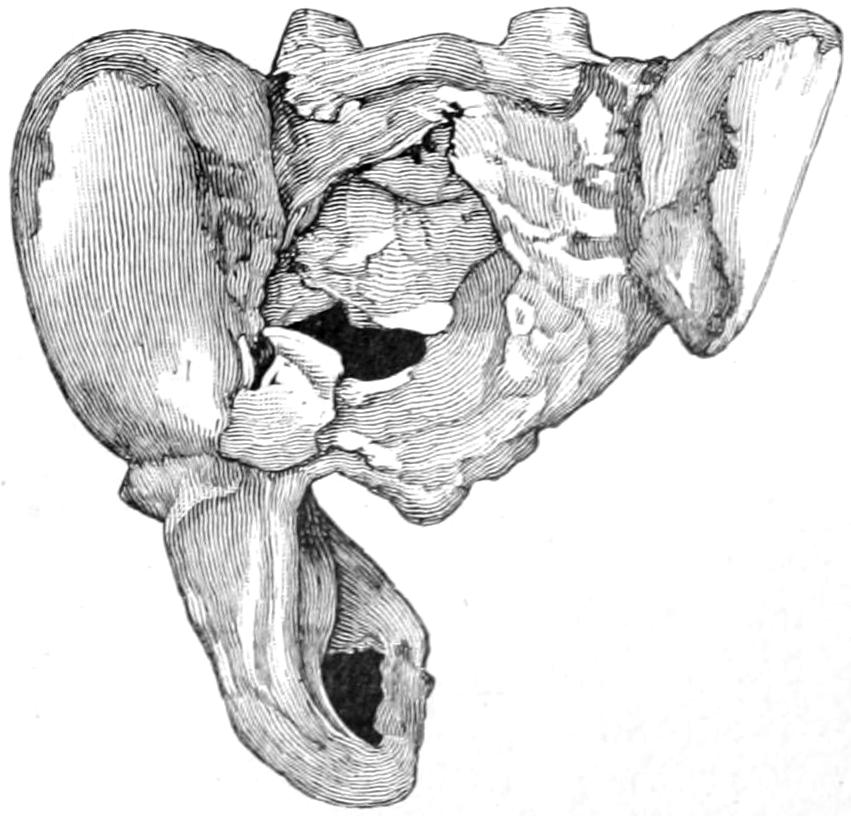

Within a few years a peculiar form of intense anemia has been described by Banti and others, and is often spoken of as splenic anemia or Banti’s disease. It is characterized by three stages: first, of splenic enlargement and anemia; second, a transitional stage; third, a stage of ascites which increases up to death. It is quite closely allied to Hanot’s hypertrophic cirrhosis of the liver. It is quite generally regarded as an example[32] of an infection by some as yet unknown organism. It is of interest to the surgeon because if the spleen is removed early there are fair prospects of recovery.